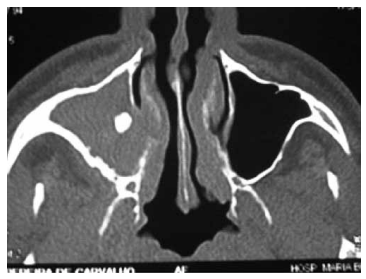

Paciente com obstrução nasal e rinorreia purulenta há 4 meses realiza a tomografia computadorizada (TC) a seguir. Assinale a alternativa correta com relação à principal hipótese diagnóstica.

Provas